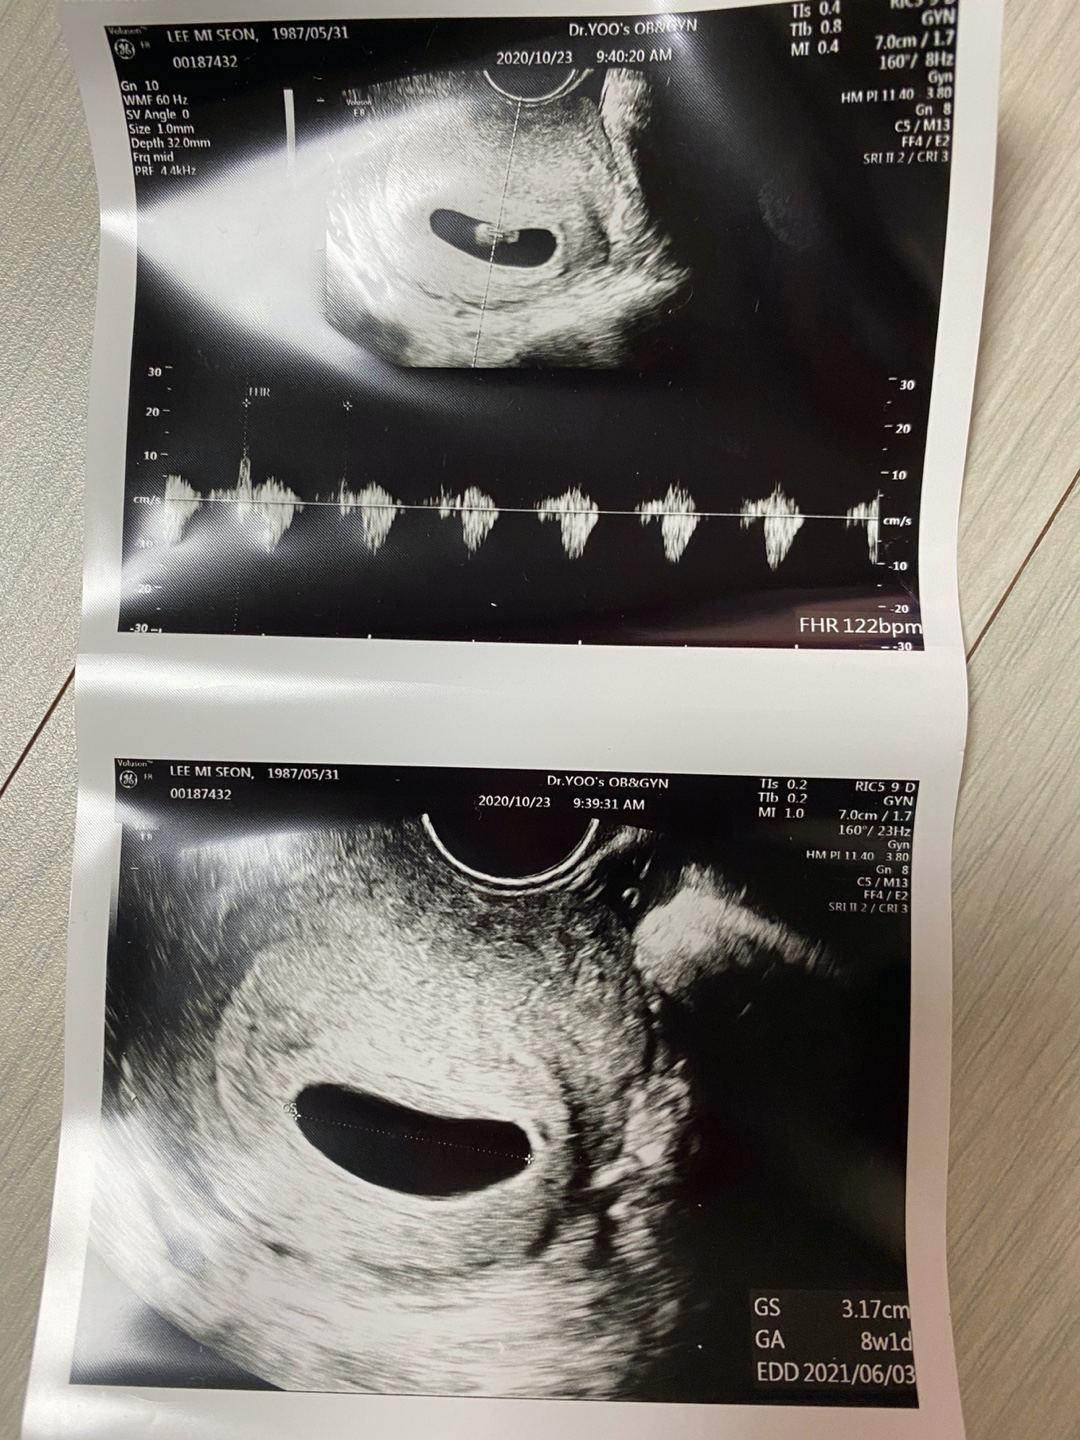

뒤이어 초음파를 보는데 아기집은 더 커져있었고 집만 있었던 공간에는 1cm도 안되는 6주차 작은 아기가 있었고 난황도 있었다.

선생님은 6주4일 날짜를 확인해주시고 내년 6월14일 예정일과

주수에 맞춰 아기집도 아기 크기도, 심장 소리도 좋다고 했다.